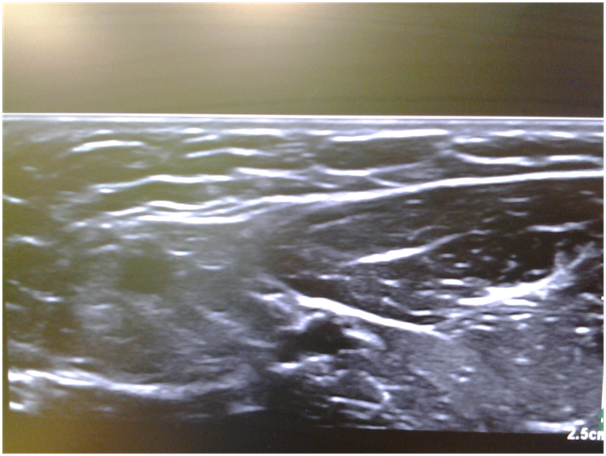

• Example of surgery at the distribution of lateral cutaneous nerve of the forearm and sonoanatomy as well as nerve block.